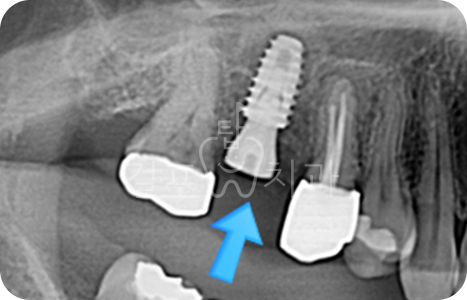

• 치아 파절로 내원하신 분입니다. 잇몸뼈가 튼튼하신 분으로 발치즉시 임플란트가 가능하였습니다.

Before

After

• 치아 뽑은 자리 잇몸염증이 매우 심한 상태였습니다. 잇몸상태가 좋지 않아도

발치 즉시 임플란트를 시도할 수 있습니다. 다만, 2~3달 지난 후 수술한다면 더 안전하므로 이런 경우 즉시 식립을 추천드리지 않습니다. 발치 몇 달 후 상악동 거상술과 뼈이식 임플란트를 함께하여 수술을 완료하였습니다.